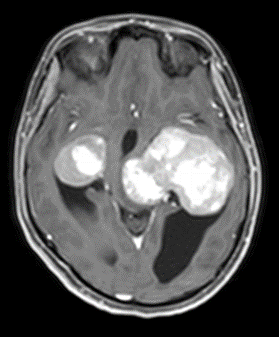

MRI outside hospital was done which was re-reported in our centre as Bilateral temporal lobe enhancing lesions. The left temporal lobe mass was larger in size and causing right-sided midline shift causing compression of the third ventricle with upstream hydrocephalus and transependymal seepage. These masses were reported as of neoplastic etiology, likely low-grade gliomas. Then MRI Brain with contrast was repeated which showed Bilateral intraventricular masses which are more or less stable in sizes causing hydrocephalus and compression effect at the level of the third ventricle towards the right side. Differentials included intraventricular tumors. No adjacent invasion is seen.

Figure 2: Lesion on T1 post contrats axial brain MRI.

The mean age of onset with nodal disease is 20.6 years with a male to female ratio of 1.4:1 [6,17]. Patients who develop intracranial involvement, however, become symptomatic at a mean age of 34.9 years, with a strong male preponderance. In intracranial RDD, the most involved structures are the suprasellar region, cerebral convexity, parasagittal region, cavernous sinus, and petroclival region [18,19]. Radiologically, the typical MRI findings include isointense to hypointense T1-weighted signals and hyperintense T2-weighted signals with homogeneous enhancement post-contrast. Bitemporal lesions often exhibit a dural-based, meningioma-like appearance [20]. Intracranial RDD is commonly confused with meningioma and requires tumor histopathology and immunohistochemistry for its definitive diagnosis.